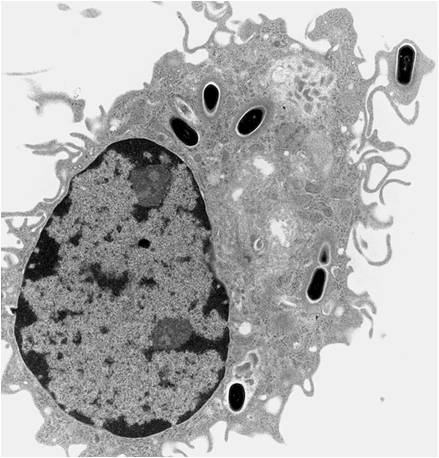

Additionally, after adhering to the surface macrophages’ cytoskeletons can remodel to allow for spreading over the surface of the material. In this manner, macrophages completely surround the material in a short period of time. Depending on material properties, this can be very harmful or fairy benign. The most harm tends to occur when macrophages detect large particles. One macrophage alone can only phagocytose very small particles (<5 μm). Larger particle sizes (>10 μm) induce the formation of foreign body giant cells (FBGCs).